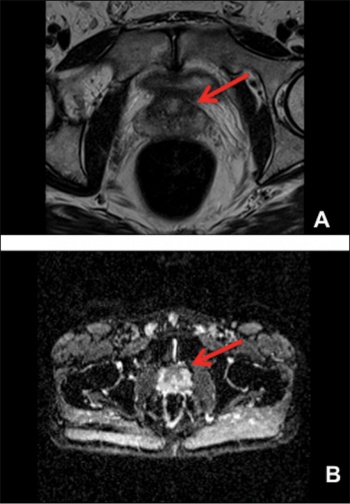

Figure 1. Image A, B and C demonstrate a lesion in the left apex of the prostate with diffusion anomalies present in image D

The patient undergoes a standard 12 core transrectal guided (TRUS) prostate biopsy and additional cores targeted at the abnormality in the left apex. All cores from the left side of prostate show Gleason 4+4 prostate cancer (WHO Grade 4) involving from 5% to 40% of each core. Neither the MRI or bone scan suggested any extra-prostatic disease and the patient elected to undergo a radical prostatectomy with bilateral pelvic lymph node dissection with preservation of the right sided nerve bundle. The surgical pathology report confirms a fully resected lesion with negative margins and nodes. He made a good functional recovery and has remained free of biochemical recurrence for 12 months.